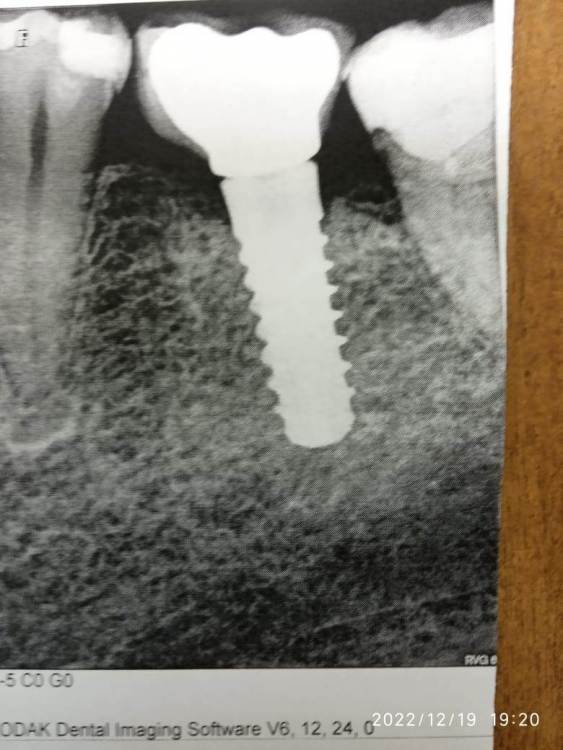

Julia Leykina Опубликовано 20 декабря, 2022 Поделиться Опубликовано 20 декабря, 2022 (изменено) Уважаемые доктора, взываю к вашему коллективному разуму. Почти 10 лет назад мне поставили имплант (нижняя левая шестерка) - в Испании, потому что на тот момент мы с семьёй проживали там. Имплант отлично и быстро прижился, и все эти годы я не знала забот, и даже успела забыть, что это не мой собственный зуб. На днях почувствовался некий дискомфорт, удалось понять, что расшатался винт, и я сразу помчалась к стоматологу. Хирург сказал, что сам имплант в отличном состоянии (фото рентгеновского снимка прилагаю), а ортопед оказался в замешательстве, потому что была неизвестна марка устройства. Я срочно списалась с испанским дантистом, который ставил имплант, но пока списывалась, ортопед попытылся что-то сделать, и винт окончательно сломался. Пришлось снять коронку (доктор наложил некую временную пломбу типа силиконовой "нашлёпки" для защиты импланта). Испанский доктор написал, что у меня стоит имплант Klockner, модель KS2, к нему нужна отвертка 1, 70. Печаль в том, что в московской клинике (и похоже во всей РФ) с такими имплантами никто не работал, и ни нужных винтов, ни инструментов к ним - просто нет. Во всём интернете поисковым запросом мне удалось найти всего два русскоязычных сайта с упоминанием этого типа имплантов. На всякий случай: https://www.medicalexpo.ru/prod/klockner-sa/product-72982-890567.html Отсюда можно заказать из Испании целый имплант, списавшись с фирмой (и то не факт, что именно сейчас это возможно, в нынешней ситуации), а мне нужен только винт и пара инструментов. https://stomik39.ru/implantaciya-zubov/zub-implanty/zubnye-implanty Это сайт клиники в Калининграде, в самом конце страницы краткая информация об этом импланте, авторс статьи - хирург Туров Дмитрий Валентинович. Впереди Новый год, а мой главный жевательный зуб в буквальном смысле оказался на полке. :(( Когда я ставила имплант в Испании. то даже не подозревала, что может возникнуть такая проблема. Возможно ли её как-то решить, исходя из вашего опыта? Доктор-ортопед сказал мне список инструментов и материалов, которые я должна раздобыть. Это динамометричекий ключ, отвёртка (соответствующая), винт трансокклюзионный, а если менять коронку (хотя мне не хотелось бы), то ещё и аналог имплантата, трансфер, основание титатовое или кобальто-хромовый сплав и ещё один винт. И это не было бы такой уж нерешаемой проблемой, если бы не всем известная ситуация. То есть я не могу перевести туда деньги, а они, скорее всего, не смогут мне это отправить по почте (экспресс-почте или т.п.). Теоретически я могу попросить друзей в Испании забрать всё это за их счёт, но с отправкой может оказаться всё непросто. Нет ли ещё какого-то решения? Например, найти совместимый с этим имплантом винтик или ещё что-то? Возможно, в вашей практике или в практике ваших коллег случался такой вид импланта и остались какие-то "запчасти"? Что вообще можно сделать в моём случае? Обидно, мне этот "зуб" весьма недёшево обошёлся. А может... вот, к примеру, испанцы у мужа на работе (в научной сфере) очень восхищались русской смекалкой ("русские умеют паять нержавейку!" :))). Может, и тут какие-то лайфхаки, не очевидные, возможны? Очень прошу откликнуться и любых, даже на первый взгляд абсурдных, советов! ? Изменено 20 декабря, 2022 пользователем Julia Leykina Опечатки Ссылка на комментарий